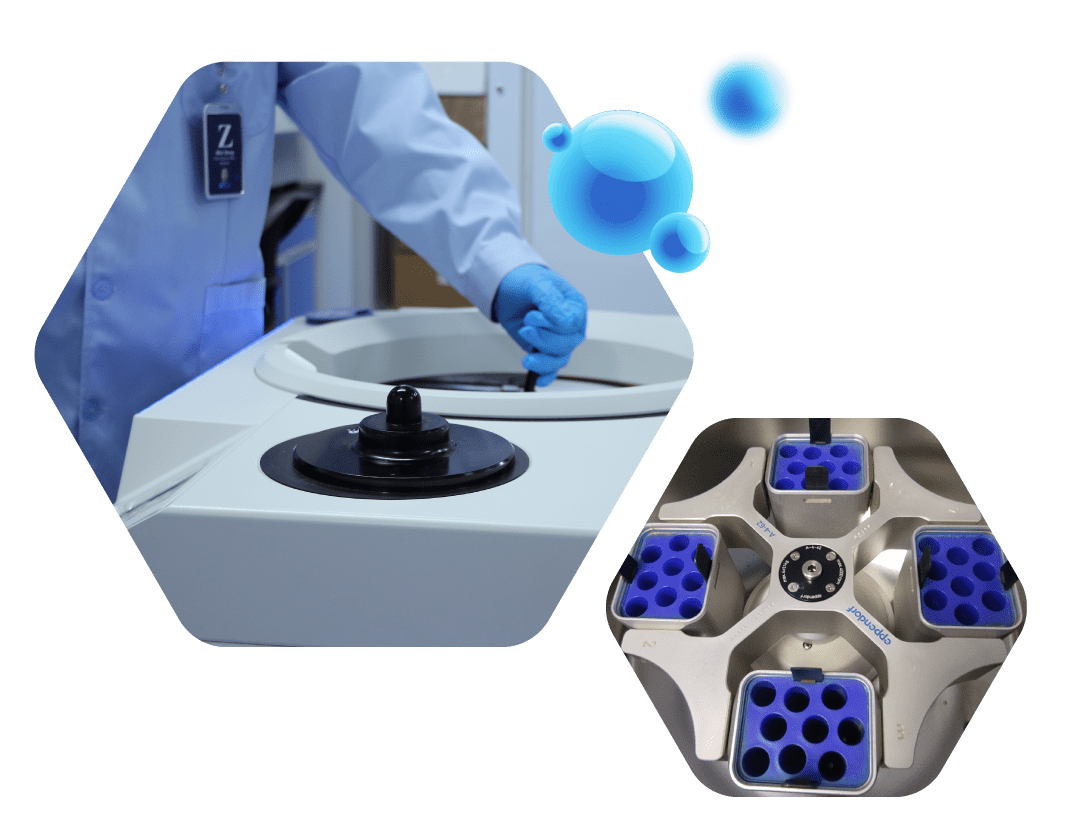

EVs Isolation Services

With an unwavering commitment to excellence, Shengranbiotech? offers you the opportunity to access exosomes from a wide range of biological samples, empowering your research endeavors with versatility and precision. Whether you're pursuing biomarker discovery, functional studies, or comparative analysis, our comprehensive services ensure that you have the right exosome samples to fuel your research goals.

EVs Purification Services

sEVs, which are freely available in plasma and other body fluids, have attracted a great deal of interest as therapeutic and diagnostic biomarkers. With years of experiences in exosome technology, Shengranbiotech has developed validated protocols to purify exosomes from both plasma and other body fluids with decreased co-purification of non-exosomal proteins.